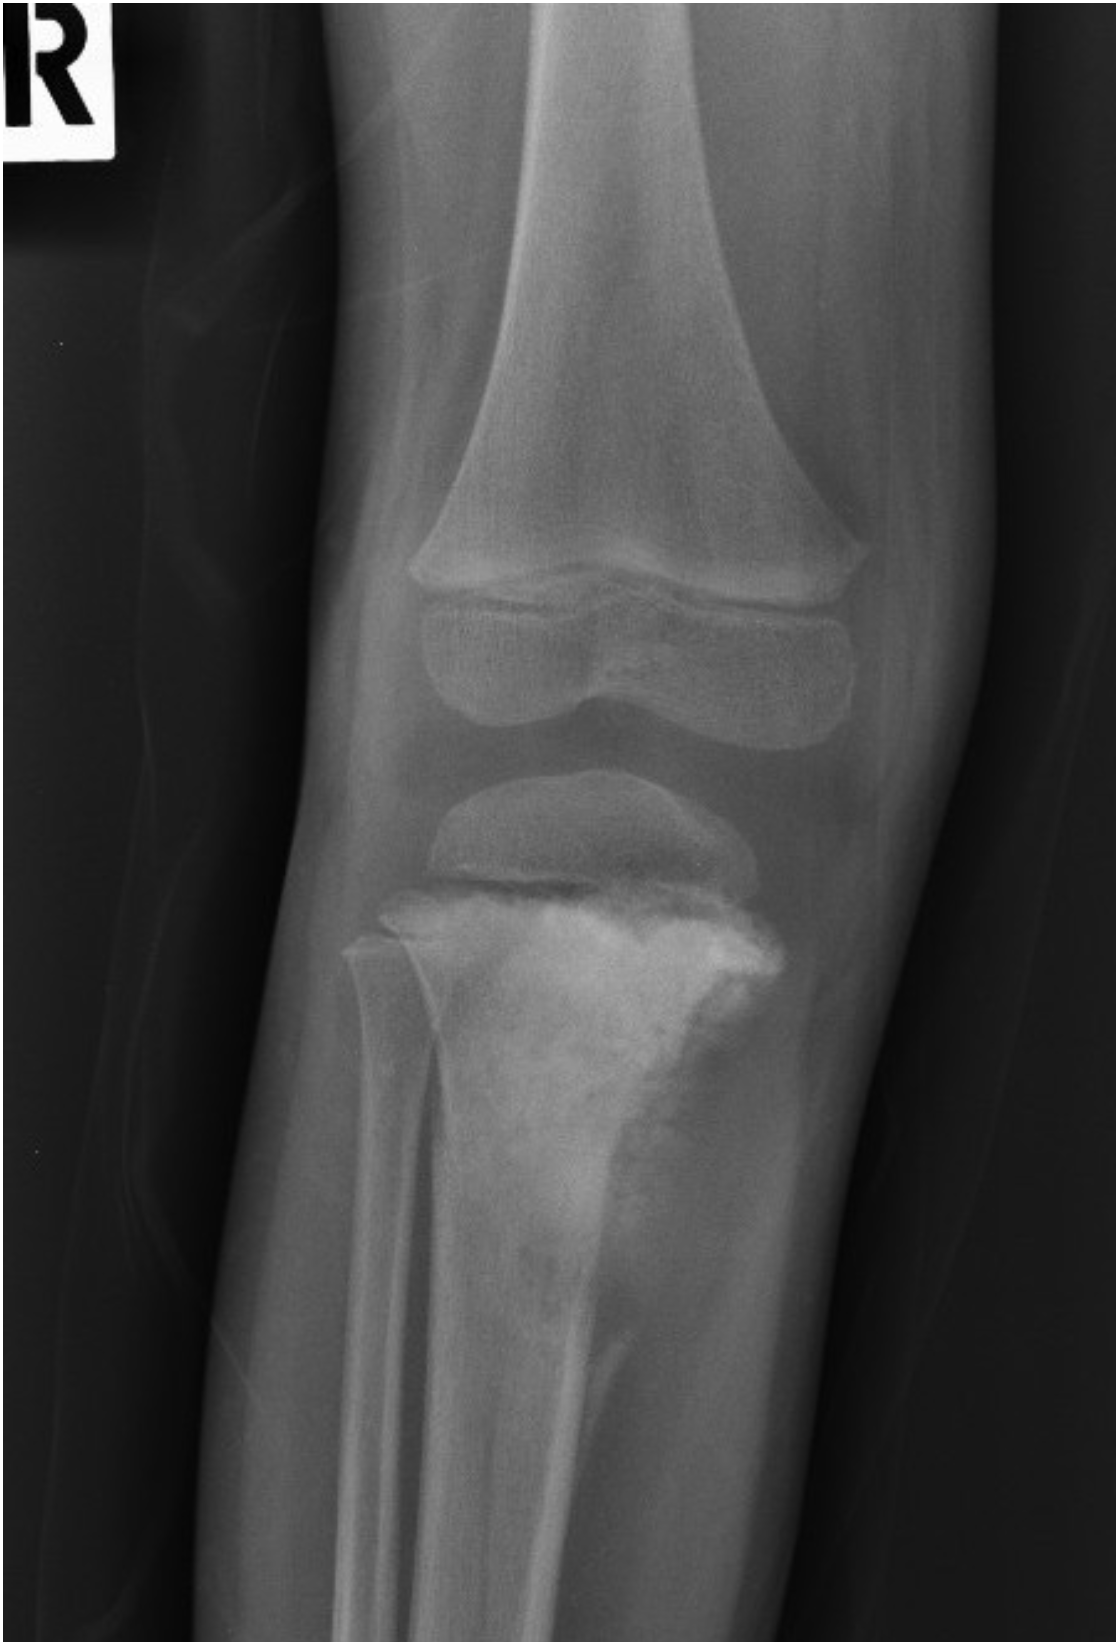

Right knee radiograph in frontal projection: An ill-defined sclerotic lesion in the dia-metaphyseal region of proximal tibia, with osteoid matrix formation. It has a wide zone of transition. Elevated periosteal reaction at the inferomedial cortex of the proximal diaphysis (Codman’s triangle). Minimal extraosseous/soft tissue extension at the medial aspect of the lesion. No intra-articular extension.

*Image retrieved from PACS USM Workflow Manager

- Image description by Dr Fattah Rahiman Ghazali (Radiologist)